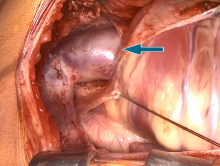

The patient was taken electively to the operating room. After full median sternotomy, the vertical vein was dissected free. After heparinization, bicaval cannulation was performed. During cooling to mild hypothermia, the pulmonary venous confluence posterior to the left atrium was dissected free. The aortic X–clamp was applied, and low-volume crystalloid cardioplegia solution was given with immediate cardiac arrest.

The right atrium was opened with an incision using an 11 blade and extended with Metzenbaum scissors. The left atrium was inspected through the large ASD. The venous confluence was opened using an 11 blade, and incision extended with Metzenbaum scissors. At this point, it is important not to extend the incision into the individual pulmonary vein orifices. This leads to a higher risk of pulmonary vein stenosis. The posterior wall of left atrium was opened at the corresponding level to the venous confluence. It is important that both incisions are made as parallel as possible. An anastomosis was fashioned between pulmonary confluence and the posterior wall of the left atrium. At this point, suturing must be performed with an inverting running suture line working inside at the pulmonary venous confluence and inside the left atrium. The anastomosis was completed with an inverting running suture in the same fashion. The tip of the sucker was used to check the individual pulmonary vein orifices. The ASD was closed with a bovine pericardial patch. The final adjustment of the patch was being made. The ASD closure was completed with a running suture. The right atrium was closed with a running paroxysmal depolarizing shift suture. The X–clamp was released, and the heart started beating spontaneously. Pulmonary artery pressure was measured directly into the pulmonary trunk after completion of the operation and revealed normal pulmonary pressures. The drainages and pacing wires were placed in the standard fashion. Color doppler demonstrated a laminary flow at the site of anastomosis.